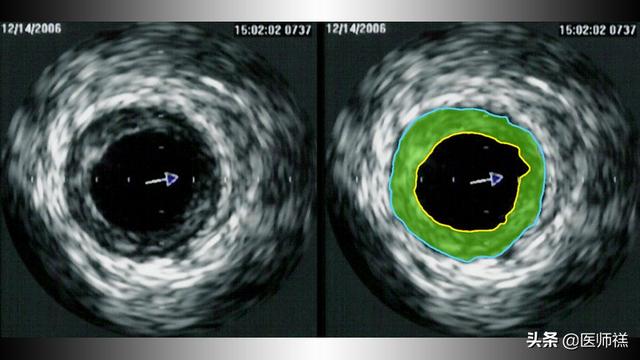

L'insuffisance de l'apport sanguin au cœur est également appelée cliniquementischémie myocardiquequi signifie généralement donnerRésultat d'une obstruction partielle ou complète des artères et des veines coronaires qui alimentent le cœur en sang.comme dans l'image ci-dessous.

Laissez-moi d'abord vous expliquer quelque choseLe concept des artères coronairesNous parlons deArtères et veines coronairesIl est en fait responsable de l'approvisionnement en sang des cellules du muscle cardiaque comme uncouronneLes mêmes vaisseaux sanguins. Les artères coronaires, par exemple, naissent à la racine de l'aorte dans le corps humain et se divisent en branches gauche et droite qui se répartissent sur la surface du cœur pour l'alimenter en sang. Les vaisseaux coronaires présentent l'avantage d'assurer l'irrigation sanguine du cœur :Les artères coronaires offrent moins de résistance au sang.Moins de 5 % de la résistance coronarienne globale afin d'assurer un apport continu de nutriments aux cellules du muscle cardiaque. Et une fois que cesObstruction partielle ou complète d'un vaisseau sanguinCela peut conduire à une situation où le cœur n'est pas suffisamment alimenté en sang.